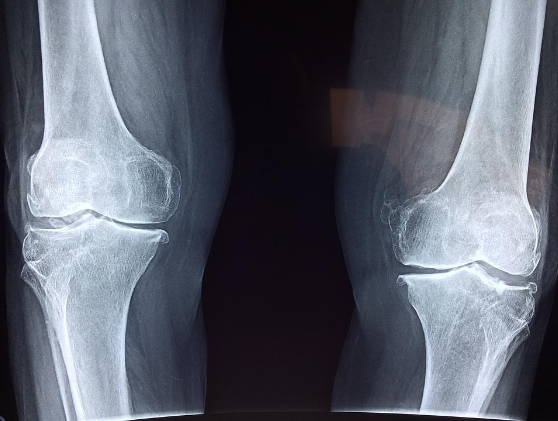

3. 관절 건강, 근육 부상 방지

관절에 부담을 주지 않으면서 관절을 운동시킬 수 있고 근육의 부상확률을 줄이는데 효과가 있습니다.

규칙적으로 걷는 사람들의 경우 관절의 통증이 적고 부상 확률이 낮은 경향이 있습니다. 규칙적인 걷기는 심장 근육을 강화시켜 자연스럽게 혈압을 낮춥니다. 또한 규칙적으로 걷는 것은 다리, 팔 및 신체의 다른 부분에 근육을 형성합니다.

다른 효과로 운동할 때 피로에 대한 저항력이 높아져 나이가 들어도 건강을 유지할 수 있습니다. 따라서 걷기는 질병이나 부상의 위험을 줄이는 동시에 건강을 유지하는 훌륭한 방법 중 하나입니다.